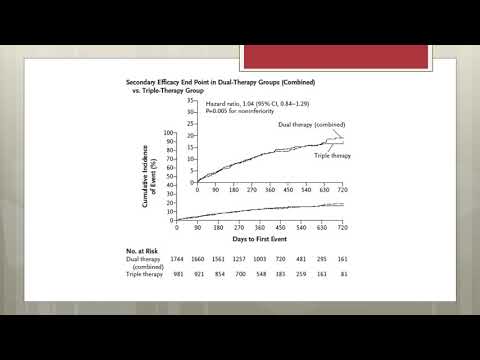

Terapia antitrombótica en pacientes con FA post ATC. Dra. Lucía Helguera. Residencia de Cardiología. Hospital C. Argerich. Buenos Aires